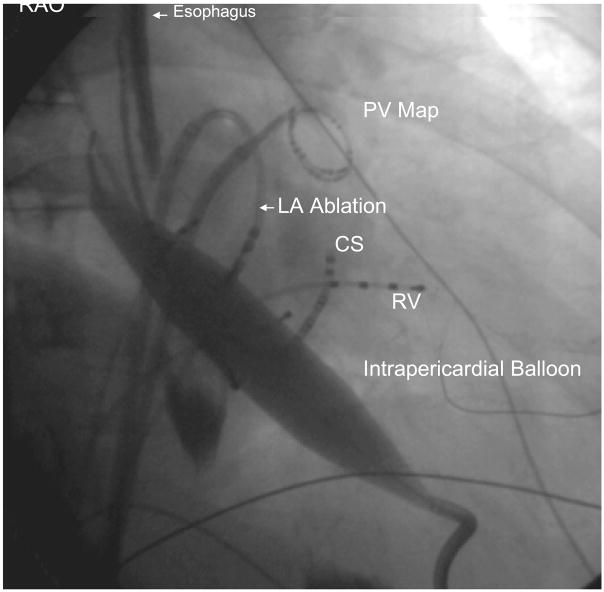

Figure 2. (A) Left anterior oblique (LAO) and 2 (B) Right Anterior Oblique (RAO) images of catheter and balloon position during isolation of left inferior pulmonary vein.

Epicardial access to the oblique sinus allowed positioning of an intra-pericardial balloon over a guidewire. After the balloon was manipulated to lie between the left atrium and esophagus at the site of intended endocardial ablation, it was inflated to increase the separation between esophagus and ablation catheter, which was positioned near the ostium of the left inferior pulmonary vein. PV Map = pulmonary vein mapping catheter, LSPV = left superior pulmonary vein, RA = right atrial catheter, RV = right ventricular catheter, ICE = intracardiac echocardiography catheter, His = His bundle catheter, CS = coronary sinus catheter.

Figure 2 B. Right Anterior Oblique (RAO) image